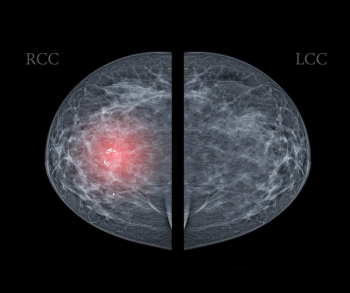

In a retrospective review involving over 2.2 million women with three consecutive biennial mammography screenings and no history of breast cancer, researchers noted that for premenopausal women with fatty breasts at baseline, increasing breast density at subsequent screenings led to significantly elevated hazard ratios ranging from 1.45 to 1.93 for the risk of breast cancer.